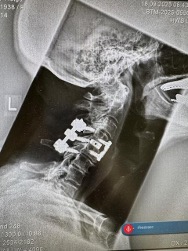

Case3 Patient from Germany. cervical Fracture by Ankylosing Spondylitis patient who fell at home at home and developed unstable fracture

Here we addressed the fracture promptly and managed to stabilise it.